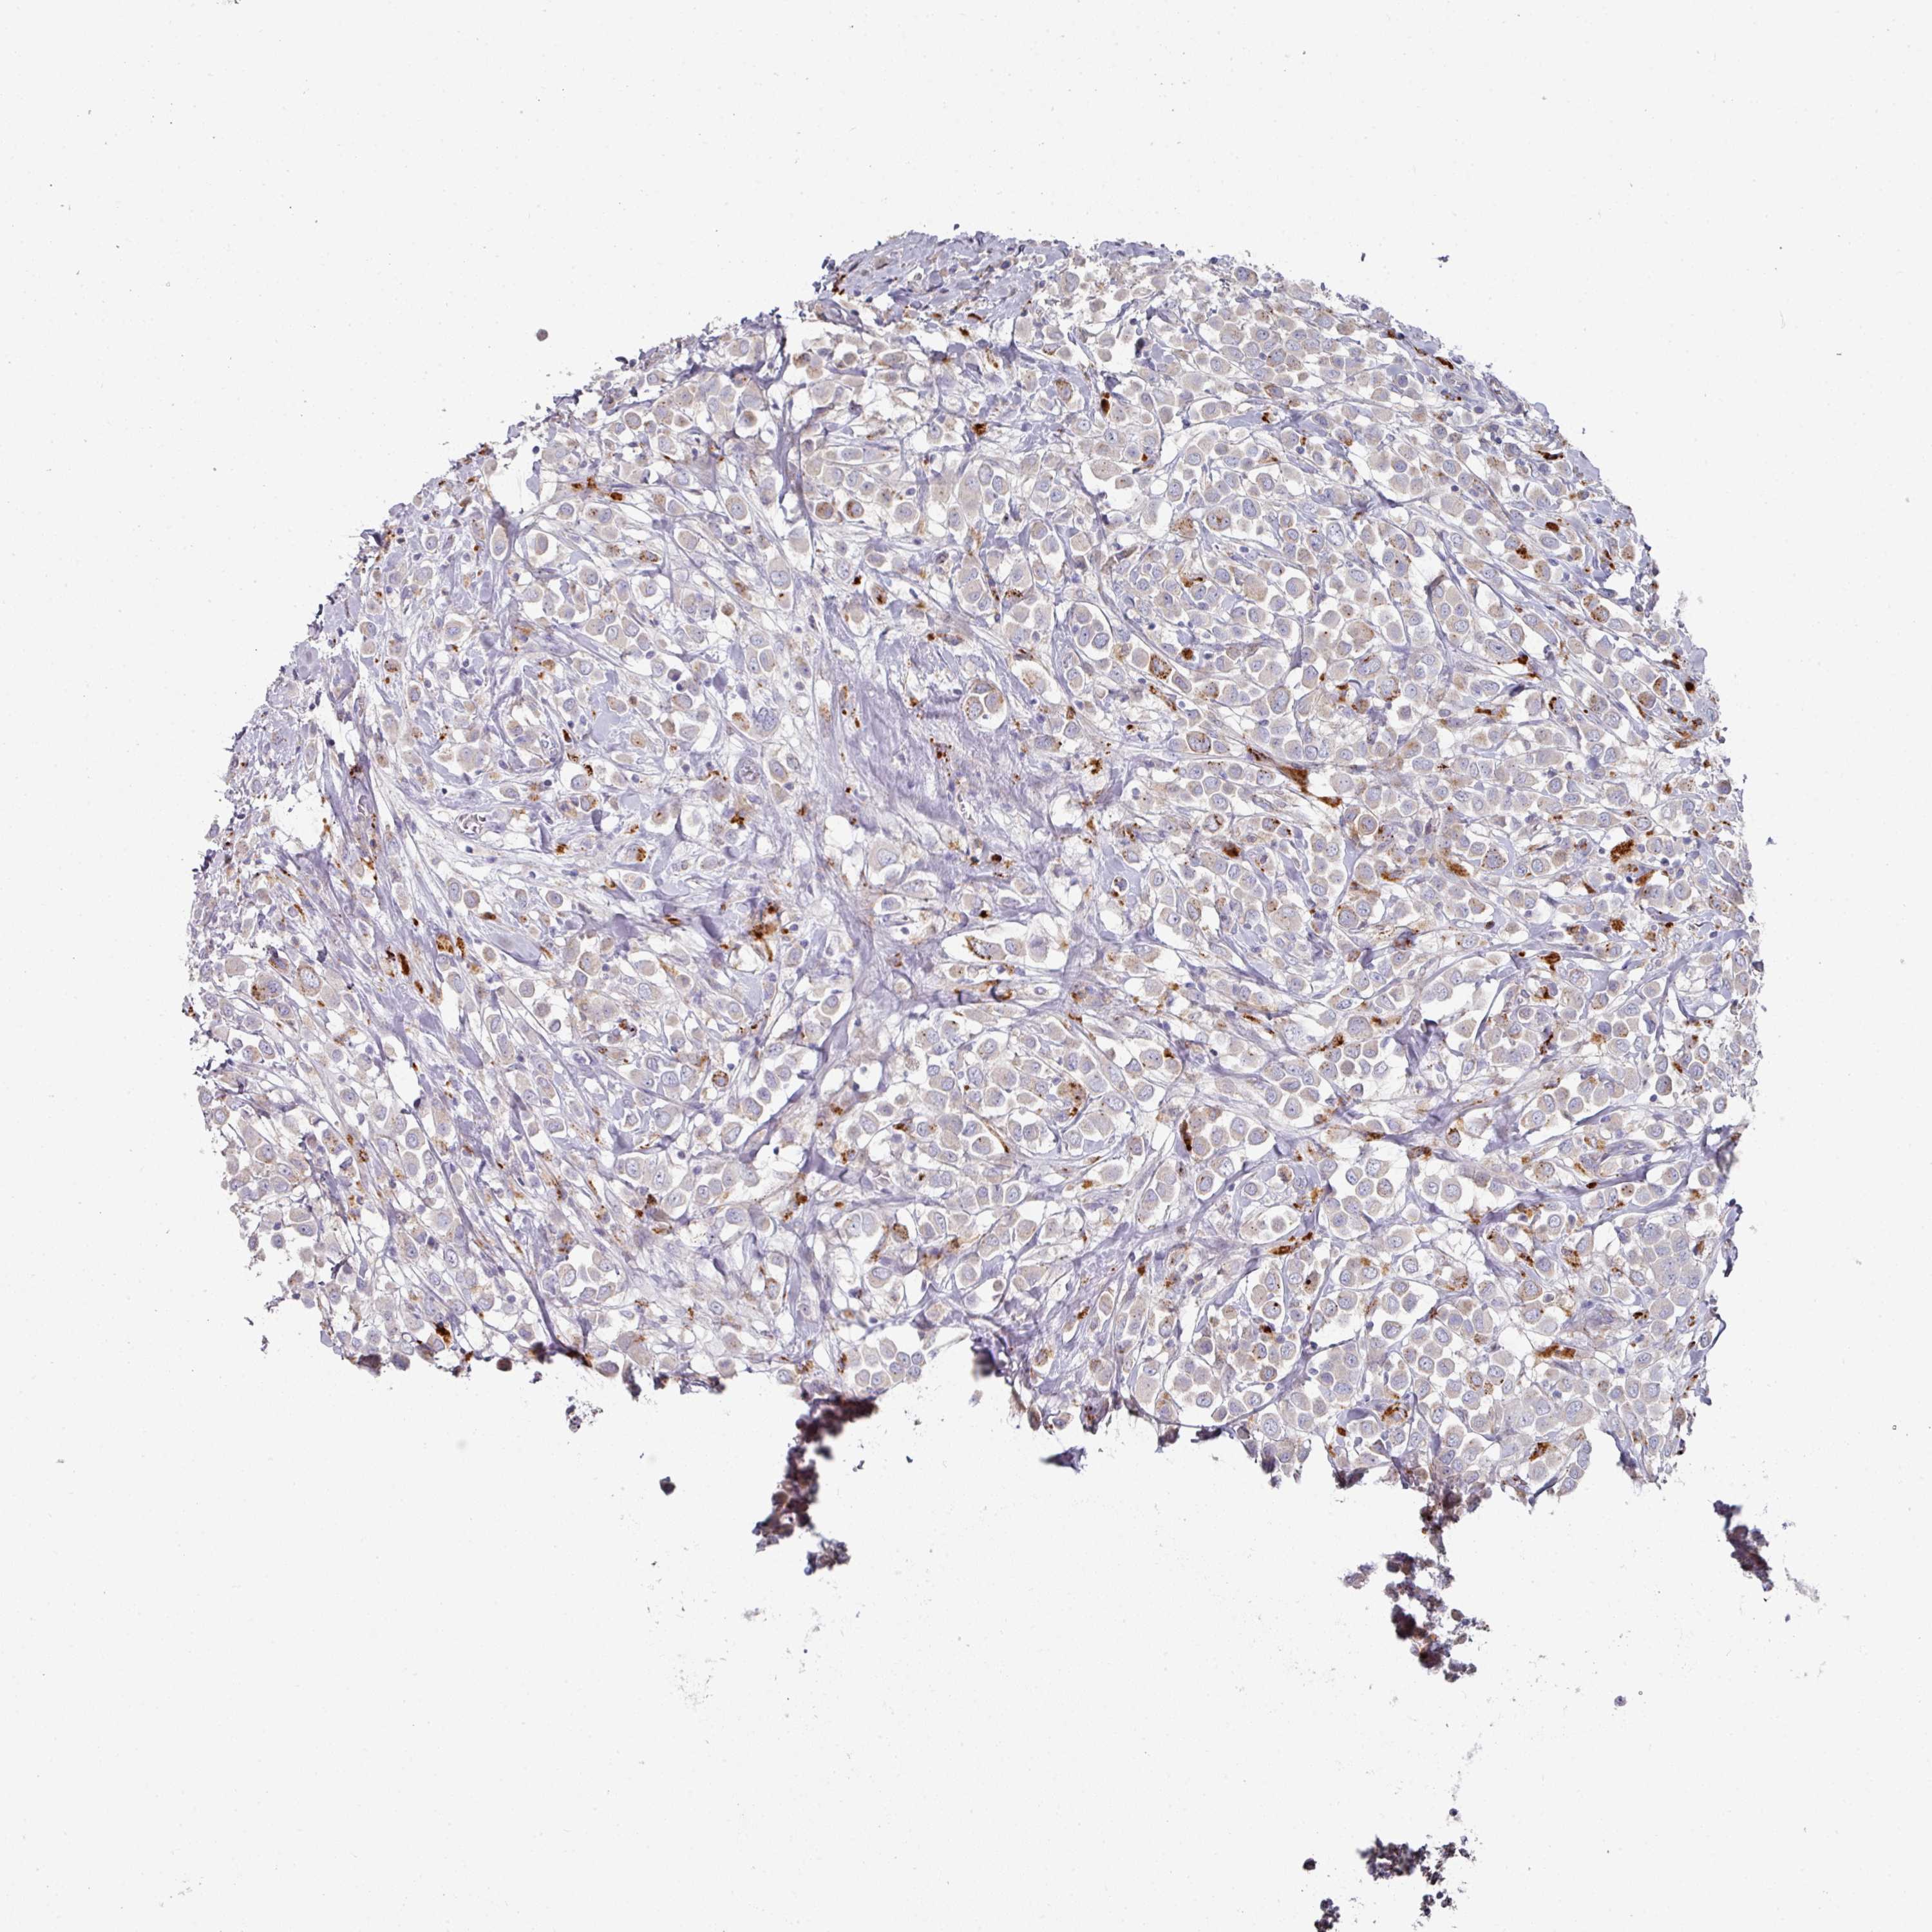

CANCER BREAST CANCER Show tissue menu

BRCA TCGA BRCA VALIDATION PROTEIN EXPRESSION

Breast cancer

Human cancer